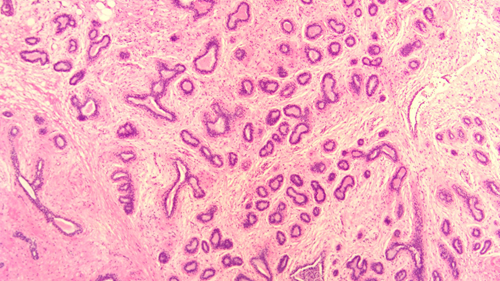

乳腺纤维腺瘤与周围正常腺体组织分界清楚,显微镜下可见其由良性的乳腺上皮和间质成分增生形成,细胞形态温和,无异型性。根据组织形态,可大致分为管内型和管周型,但分型对临床预后并无显著影响。该肿瘤经完整手术切除后,一般不会复发。

(图1:正常乳腺组织小叶)